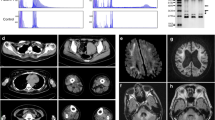

For a restricted number of patients, we had two biopsies from two different muscles including cricopharyngeal CPM, deltoid DM, sternocleidomastoid SCM, tibialis anterior TA or vastus lateralis VLM (Table 1), the CPM being the most severely affected muscle in OPMD, leading to dysphagia. When we compared TA and VLM or DTM and SCM from the same patients, the percentage of nuclei containing aggregates was not statistically different between two distinct muscle biopsies from the same patient, regardless of their proximal or distal location. The only difference was observed when measuring the number of aggregates in the affected CPM compared to the other muscle biopsy from the same patient: less aggregates were systematically observed in CPM (Fig. 4a, b). This could be due to a lower level of PABPN1 protein in pharyngeal muscle, as previously demonstrated in mouse [5]. Indeed, on a subset of muscle biopsies, we observed a low level of PABPN1 protein in human CPM muscle samples compared to SCM (Fig. 4c). Since a loss of PABPN1 also leads to muscle degeneration, we performed an embryonic eMyHC staining (a very early marker of muscle regeneration) to evaluate the level of regeneration in these muscles. We observed many eMyHC positive fibers in OPMD CPM (Fig. 4d), suggesting on-going signs of degeneration/regeneration in this muscle, although we cannot exclude the naturally co-expression of developmental MyHC in the CPM which has a specific origin comparable to the other facial muscles [55]. We cannot exclude that the low level of aggregates is due to the loss of muscle fibers.

Affected CPM contains less nuclear aggregates, low level of PABPN1 and signs of regeneration. a Comparison of the percentage of myonuclei containing aggregates in two muscles from the same patient. VLM vastus lateralis muscle, TAM tibialis anterior muscle, DTM deltoid muscle, SCM sternocleidomastoid muscle, CPM cricopharyngeal muscle. Paired t test ns non-significant; **p < 0,005. b Muscle fibers from affected CPM are smaller than those from SCM and contain less aggregrates. PABPN1: green; dystrophin: red; dapi: blue. Scale bar = 50 µm. c Western-blot analysis of the level of PABPN1 in SCM and CPM from three OPMD patients. As a reference a protein extract from skin (SK) has been loaded. Western-blot is normalized with GAPDH protein levels. The age of the patient is indicated above (y: years). d Embryonic eMyHC immunofluorescence staining on a CPM to demonstrate regenerating fibers. eMyHC: green; laminin: white; DAPI: blue. Scale bar = 50 µm

To further analyze the status of PABPN1 aggregates during muscle regeneration, we generated a human skeletal muscle xenograft model by transplanting fresh human OPMD muscle biopsy samples into the TA muscle bed of immunodeficient mice (Fig. 5a). In this xenograft model, the grafted human OPMD muscle first completely degenerates then regenerates (Fig. 5b). After grafting, OPMD human muscles display characteristic features of the disease, including ragged red fibers (Fig. 5c) and PABPN1 nuclear aggregates (Fig. 5d). We compared the percentage of myonuclei containing PABPN1 aggregates before (on frozen muscle biopsy) and after regeneration (on frozen xenograft several months post-surgery), and we observed an average of threefold lower amount of PABPN1-aggregate containing nuclei within the 3 xenografted biopsies compared to the initial biopsy (on average 2.3% after vs 8.6% before regeneration) (Fig. 5c, d), suggesting that the low level of PABPN1 aggregates in CPM could be due to the regeneration process. In this xenograft model, one PABPN1 aggregate was HSP70-positive (Fig. 5e).

OPMD xenograft model demonstrate that nuclear PABPN1 aggregates appear soon after regeneration but at a lower amount. a EDL and TA from immunodeficient mice have been removed and replaced by small muscle fascicles taken from biopsy samples (SCM) of OPMD patient. Four months later, regenerated muscle can be collected and frozen for analysis. b Regenerated human muscle tissue (derived from the OPMD patient muscle biopsies) can be differentiated from mouse using human-specific labeling of muscle fibers (hspectrin) and muscle nuclei (hlamAC). c H&E and Gomori trichrome staining on the initial biopsy and on the xenografted SCM muscle highlighted features of dystrophic muscle such as centronucleated fibers and rimmed vacuoles. Scale bar = 50 µm. d Immunofluorescence displays nuclear aggregates on an OPMD SCM muscle biopsy prior to xenotransplantation (left) and after xenotransplantation (right). e Percentage of human nuclei containing aggregates before and after xenografting of three independents human OPMD SCM muscle biopsies. f A large nuclear aggregate containing HSP70 in the xenografted SCM muscle four months after engraftment. Scale bar = 10 µm